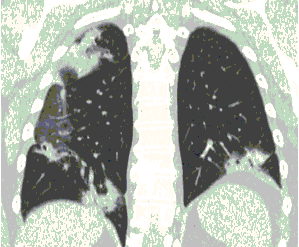

4.3. ЛУЧЕВАЯ ДИАГНОСТИКА COVID-19

Методы лучевой диагностики применяют для выявления COVID-19 пневмоний, их осложнений, дифференциальной диагностики с другими заболеваниями легких, а также для определения степени выраженности и динамики изменений, оценки эффективности проводимой терапии.

КТ имеет высокую чувствительность в выявлении изменений в легких, характерных для COVID-19. Применение КТ целесообразно для первичной оценки состояния ОГК у пациентов с тяжелыми прогрессирующими формами заболевания, а также для дифференциальной диагностики выявленных изменений и оценки динамики процесса. КТ позволяет выявить характерные изменения в легких у пациентов с COVID-19 еще до появления положительных лабораторных тестов на инфекцию с помощью МАНК. В то же время, КТ выявляет изменения легких у значительного числа пациентов с бессимптомной и легкой формами заболевания, которым не требуется госпитализация. Результаты КТ в этих случаях не влияют на тактику лечения и прогноз заболевания при наличии лабораторного подтверждения COVID-19. Поэтому массовое применение КТ для скрининга асимптомных и легких форм болезни не рекомендуется. При первичном обращении пациента с подозрением на COVID-19 рекомендуется назначать КТ только при наличии клинических и инструментальных признаков дыхательной недостаточности (SpO2 < 95%, ЧДД > 22).

3. Применение лучевых методов у пациентов с симптомами ОРВИ легкой степени тяжести и стабильном состоянии пациента, возможно только по конкретным клиническим показаниям, в том числе при наличии факторов риска, при условии достаточных технических и организационных возможностей. Методом выбора в этом случае является КТ легких по стандартному протоколу без внутривенного контрастирования или РГ при ограниченной доступности КТ. Использование УЗИ в этих случаях нецелесообразно. Применение КТ исследования в сроки ранее 3 - 5 дней с момента появления симптомов заболевания, а также при отсутствии клинических проявлений поражения бронхолегочной системы является нецелесообразным. Выполнение КТ целесообразно при наличии клинических и инструментальных признаков дыхательной недостаточности (SpO2 < 95%, ЧДД > 22), либо при дифференциальной диагностике с другим заболеванием.